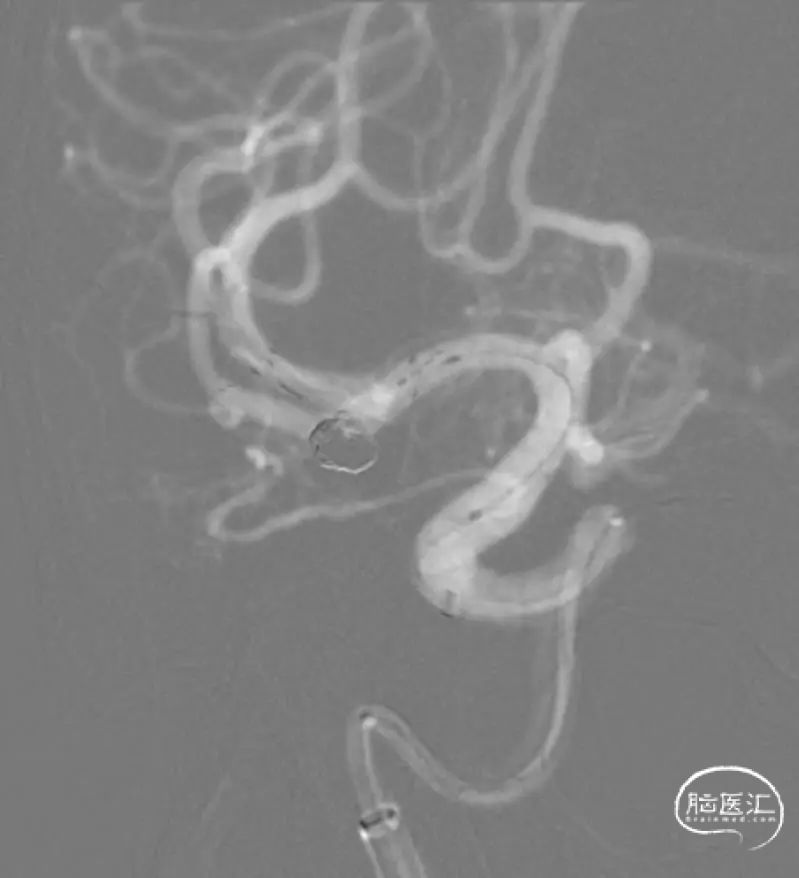

置入第2枚支架。

Neuroform Atlas 3mm×15mm,充分保护瘤颈。

支架到位。

支架释放。

结束前造影。